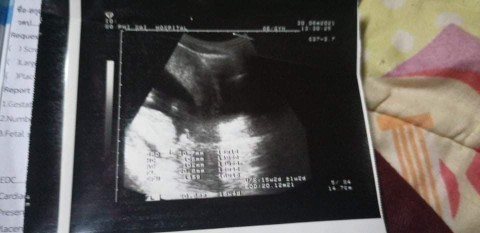

16w1วันจ้า วันที่5นัดซาวดูเพศ

บ้านนี้เจอตอน14 วีคค่ะ เพศชาย